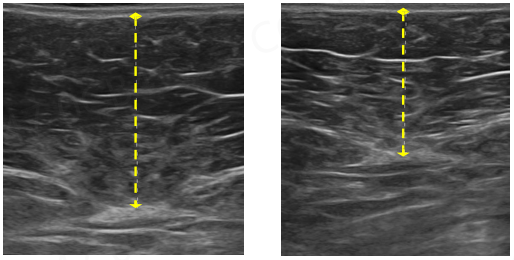

相比吸脂的即刻相关,酷塑瘦身是循序渐进的,毕竟凋亡脂肪新陈代谢排出是需要时间的,大约在2月左右能看到明显变小,脂肪层明显变薄。